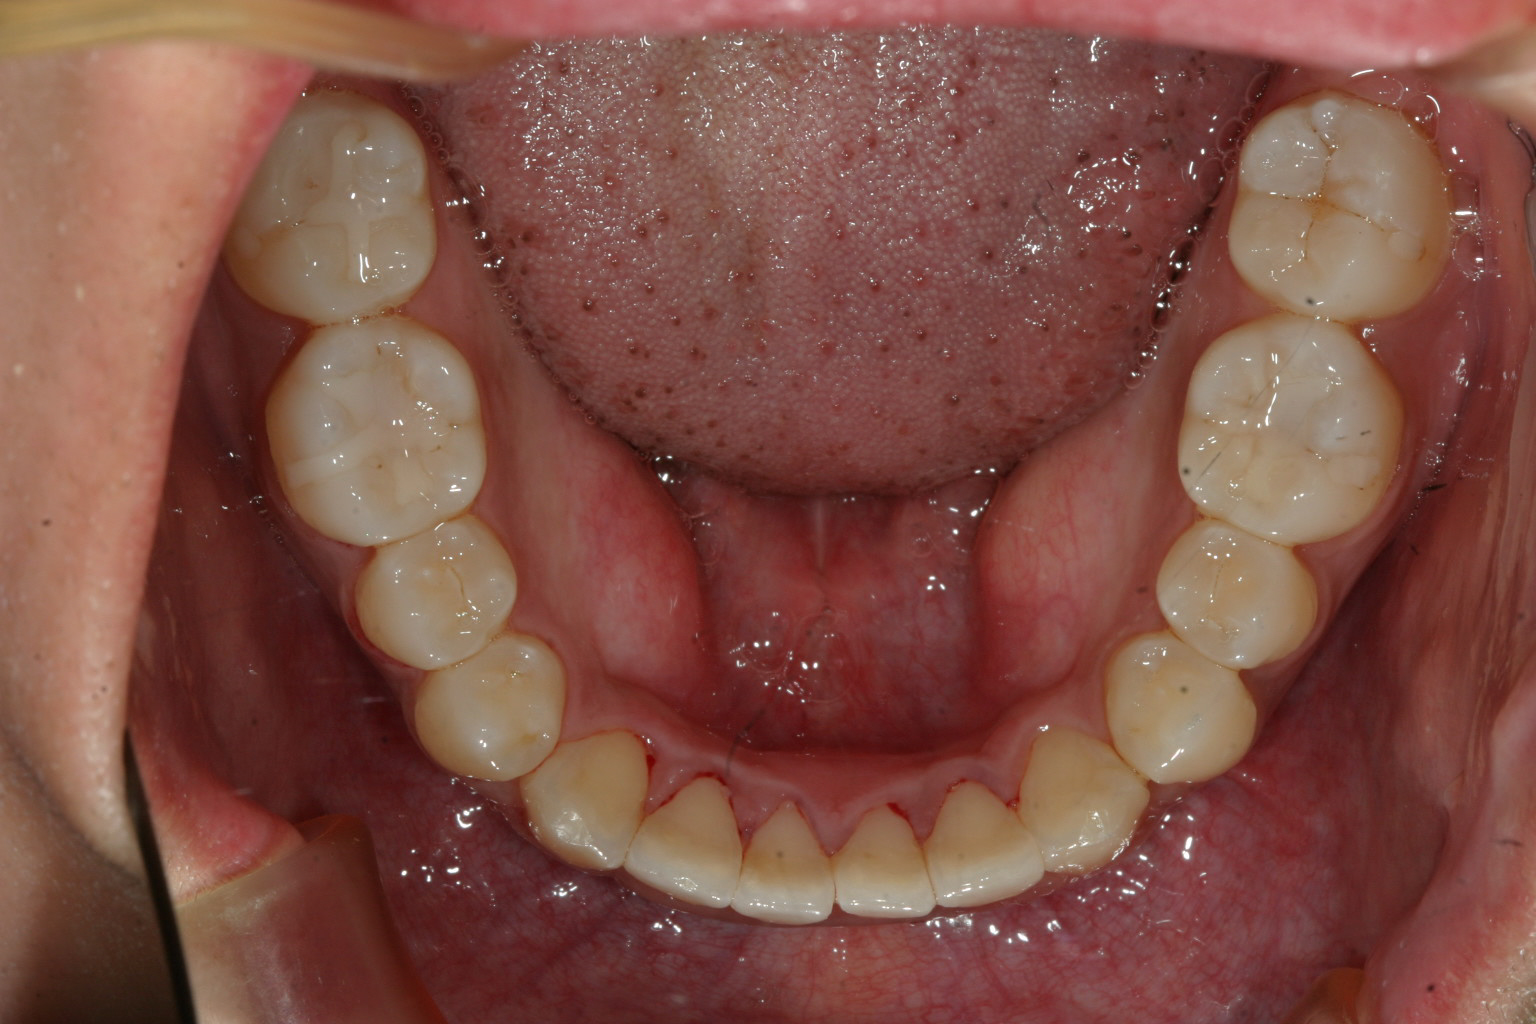

左の犬歯が完全にはじき出されています。

前歯部に叢生が見られます。

飛び出た犬歯もアーチに入り綺麗に並びましたね!

叢生も綺麗になっています。

上下の被蓋関係も良好です。